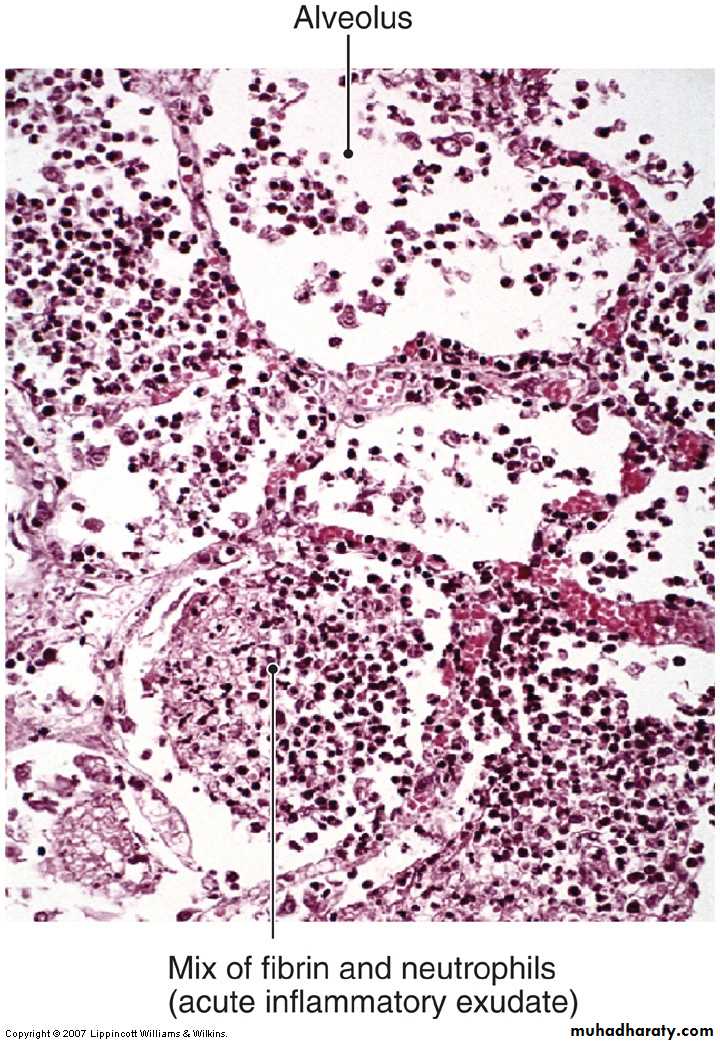

histologic spectrum of pneumonia may vary from .fibrinopurulent (acute bacterial)

Acute bacterial pneumonias can present as one of two anatomic and radiographic patterns, referred to as bronchopneumonia and lobar pneumonia.1- Bronchopneumonia implies a patchy distribution of inflammation that generally involves more than one lobe . This pattern results from an initial infection of the bronchi and bronchioles with extension into the adjacent alveoli.

2-lobar pneumonia the contiguous airspaces of part or all of a lobe are homogeneously filled with an exudate that can be visualized on radiographs as a lobar or segmental consolidation Streptococcus pneumoniae is responsible for more than 90% of lobar pneumonias.

Morphology

During the first stage, that of congestion, the affected lobe(s) is (are) heavy, red; histologically, vascular congestion can be seen, with proteinaceous fluid, scattered neutrophils, and many bacteria in the alveoli. Within a few days,

the stage of red hepatization ensues, in which the lung lobe has a liver-like consistency; the alveolar spaces are packed with neutrophils, red cells, and fibrin

In the, gray hepatization, the lung is dry, gray, and firm, because the red cells are lysed, while the fibrinosuppurative exudate persists within the alveoli

Resolution follows in uncomplicated cases, as exudates within the alveoli are enzymatically digested to produce granular, semifluid debris that is resorbed, ingested by macrophages, coughed up, or organized by fibroblasts